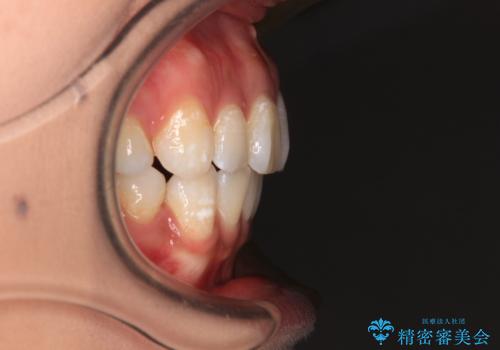

- 口元の閉じにくさを気にして来院された患者様です。

上下ともに歯列が前方に突出していたため、上下左右の第一小臼歯4本を抜去し、ワイヤー装置による矯正治療を行うこととしました。

4本の歯を抜歯したことで、飛び出していた口元が引っ込み、横顔が大きく改善されました。